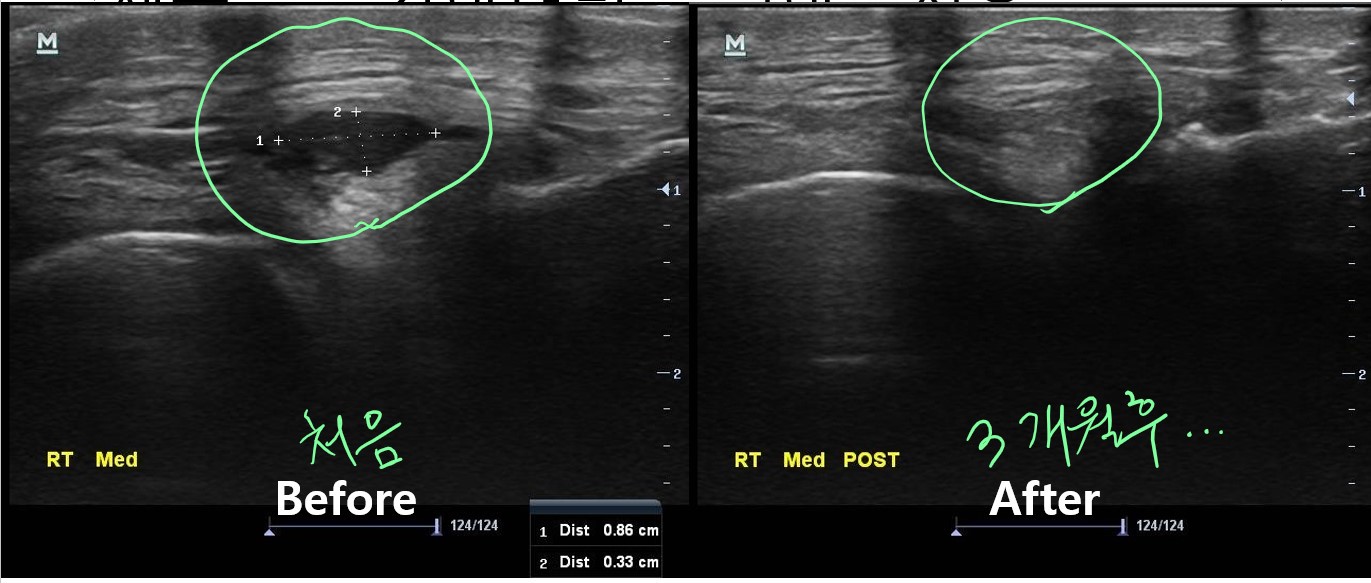

박상준 의원 병원위치, 진료시간, 연락처 등등이 궁금하면 클릭하세요. ^^ (당산 당산역 당산동 여의도 합정 목동 영등포 영등포구청 선유도 양평동 국회의사당 정형외과 야간진료 도수치료 통증의학과 박상준의원) 안녕하세요 당산 정형외과 박상준의원 박상준원장입니다. 오늘은 얼마전에 무릎이 아프다고 온 환자 이야기를 해볼까 합니다. 얼마전 중년의 환자분이 진료실로 들어오셨습니다. 나 : 안녕하세요 , 어디가 불편하세요? 환자 : 무릎이 불편합니다. 다리가 불편한지 약간 절뚝이던 남자분... 문제는 무릎이었습니다. 나 : 아픈지 얼마나 되셨나요? 다치거나 무리한게 있으세요? 다리를 많이 쓰는 일을 하시나요? 환자 : 불편한지가..... 3개월정도 되었구요... 다치거나 특별한 일은 없었습니다. 특별한 운동도 하지..